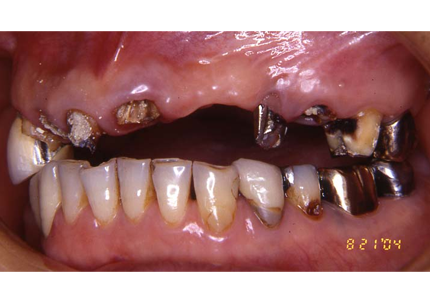

1.初診時(2006年5月)

2.上顎補綴物除去

3.上顎補綴物除去、旧インプラント除去手術後(骨吸収後)

4.前歯部骨造成(G.B.R)

5.仮歯装着歯装着